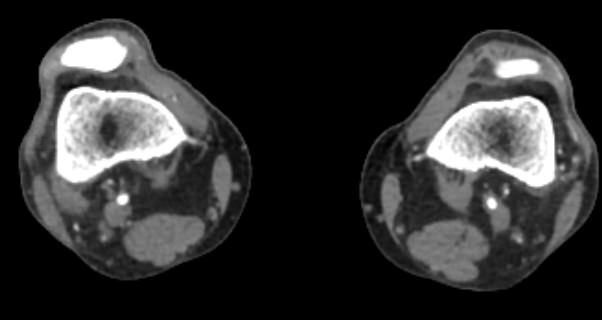

• Контрастное усиление: контрастное вещество вводится внутривенно. Это помогает улучшить видимость сосудов на изображениях.

• Сканирование: пациент должен лежать неподвижно, чтобы получить четкие изображения. Процедура обычно занимает от 15 до 30 минут.

• Высокая точность и детализация изображений.

• Возможность трехмерной реконструкции сосудов.